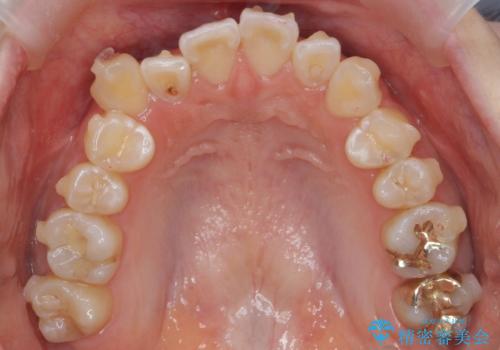

八重歯 インビザラインで抜歯矯正 ただし1本のみの抜歯で済みます

- 八重歯を治したいと来院。

古典的な治し方ですと上下左右4本抜歯してワイヤー矯正です。

今回は口元も出ていないうえに、右上のみの八重歯のため奥歯を後ろに下げて治療しました。

ただし、下の前歯は入りきらない為1本のみ抜歯しています。